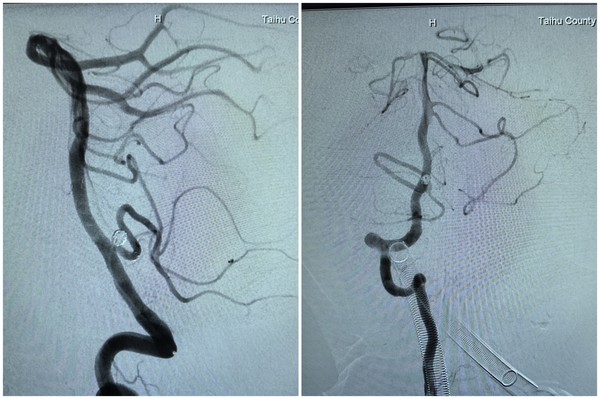

据了解,该患者此前因 “言语不清伴右侧肢体无力 1 天” 前往医院就诊,经头颅 CTA 检查提示,其右侧小脑后下动脉存在一枚直径约 4mm 的动脉瘤,且瘤颈已累及右侧小脑后下动脉。“若采用传统开颅手术,不仅创伤大,手术风险也极高。” 该院神经疾病诊疗中心主任江龙腾解释道,“小脑后下动脉负责为延髓供血,而延髓是颅内生命中枢,一旦术中出现血管破裂或栓塞,可能直接导致患者昏迷甚至死亡。” 因此,团队最终决定在 DSA(数字减影血管造影)引导下,通过微创方式精准填入栓塞材料,同时确保正常血管血流通畅。

手术当天,在 DSA 设备实时引导下,介入医生先为患者进行右侧股动脉、右侧桡动脉穿刺置管,成功建立双通道。随后,通过股动脉通路,利用翻山技术将支架微导管置入右侧小脑后下动脉;同时通过桡动脉通路,将弹簧圈微导管精准送入动脉瘤腔内。团队先填入几枚不同规格的弹簧圈,再沿支架微导管释放一枚颅内支架,实现对动脉瘤的完全覆盖。术中造影显示,动脉瘤已完全隔绝,基底动脉、右侧小脑后下动脉血流通畅,未出现血管狭窄或栓塞迹象,整个手术历时 2 小时顺利完成。